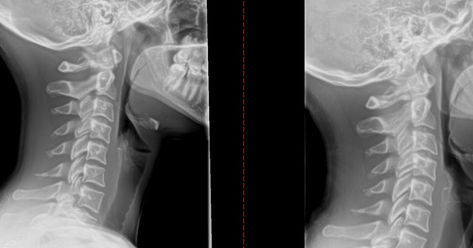

Many individuals who suffer from migraines find relief through chiropractic care. Dr. Moreland employs a holistic approach to treatment, focusing on the root cause of the problem rather than just masking the symptoms. Through gentle adjustments and targeted therapies, he aims to restore proper alignment and function to the spine, alleviating the underlying issues that can contribute to migraine headaches. Dr. Moreland focuses on restoring the normal lordotic curve of the cervical spine to help relieve headaches and neck pain.